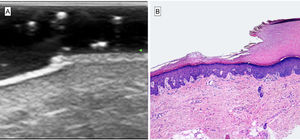

High-frequency ultrasound imaging was performed in B and Doppler color modes with a 10-22MHz linear probe (Esaote MyLab Class C, Genoa, Italy). The B-mode image revealed abrupt epidermal thinning, with structural loss in a double hyperechogenic layer that sloped to form a single hyperechogenic layer under which a subepidermal low-echogenic band (SLEB) could be seen. The Doppler color image ruled out abnormal vascularization.

The case is noteworthy for good correlation between the ultrasound images and histologic features in biopsied tissue (Fig. 2).

Correlation between ultrasound and histologic findings. A, B-mode ultrasound image, 22mHz. Area of abrupt epidermal thinning, sloping downward, with structural loss in a double hyperechogenic layer of acral skin. The image is similar to the stair-like sign. SLEB (a subepidermal low-echogenic band) can be observed under the affected epidermis. B, Histopathology shows an abrupt depression in the epidermis due to corneal layer thinning and shedding. The high correlation between ultrasonography and histology is evident.